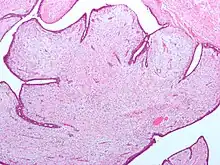

Fibroepithelial neoplasm (Phyllodes tumor).

A fibroepithelial neoplasm (or tumor) is a biphasic tumor. They consist of epithelial tissue, and stromal or mesenchymal tissue. They may be benign or malignant.[1]